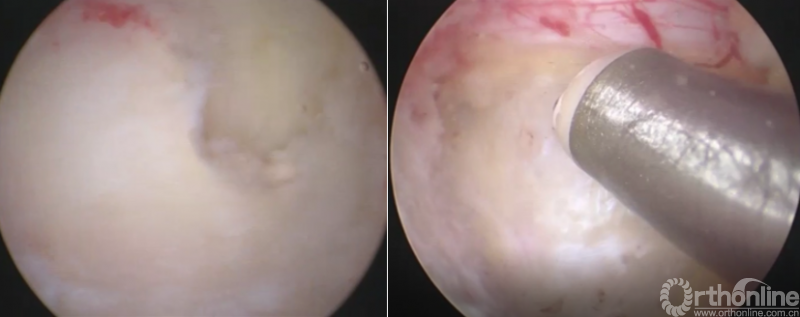

第八步“铰”:盲视下可撑开铰刀置入,撑开并处理上下终板;

第九步“填”;椎间隙填塞植骨;

第十步“置”:置入融合器、经皮钉。